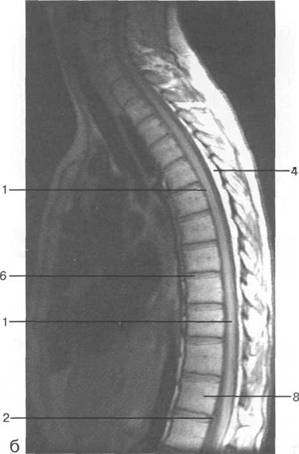

(dura mater spinalis), (arachnoidea spinalis) (pia mater spinalis).

(cavitas epiduralis),

Паутинная мозговая оболочка состоит из к 141s183b 83;еточной мембраны, к которой прикрепляется